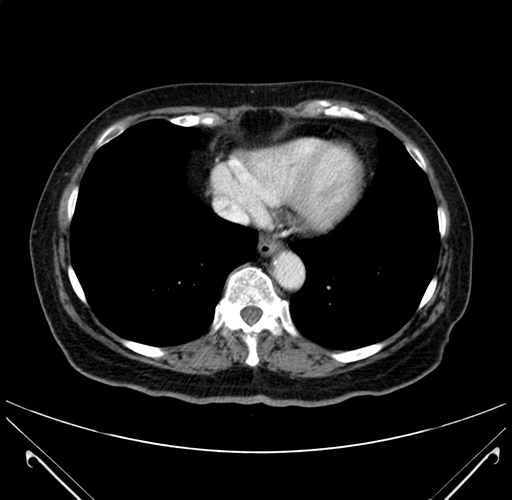

Axial Venous

Coronal Venous

MRI T1